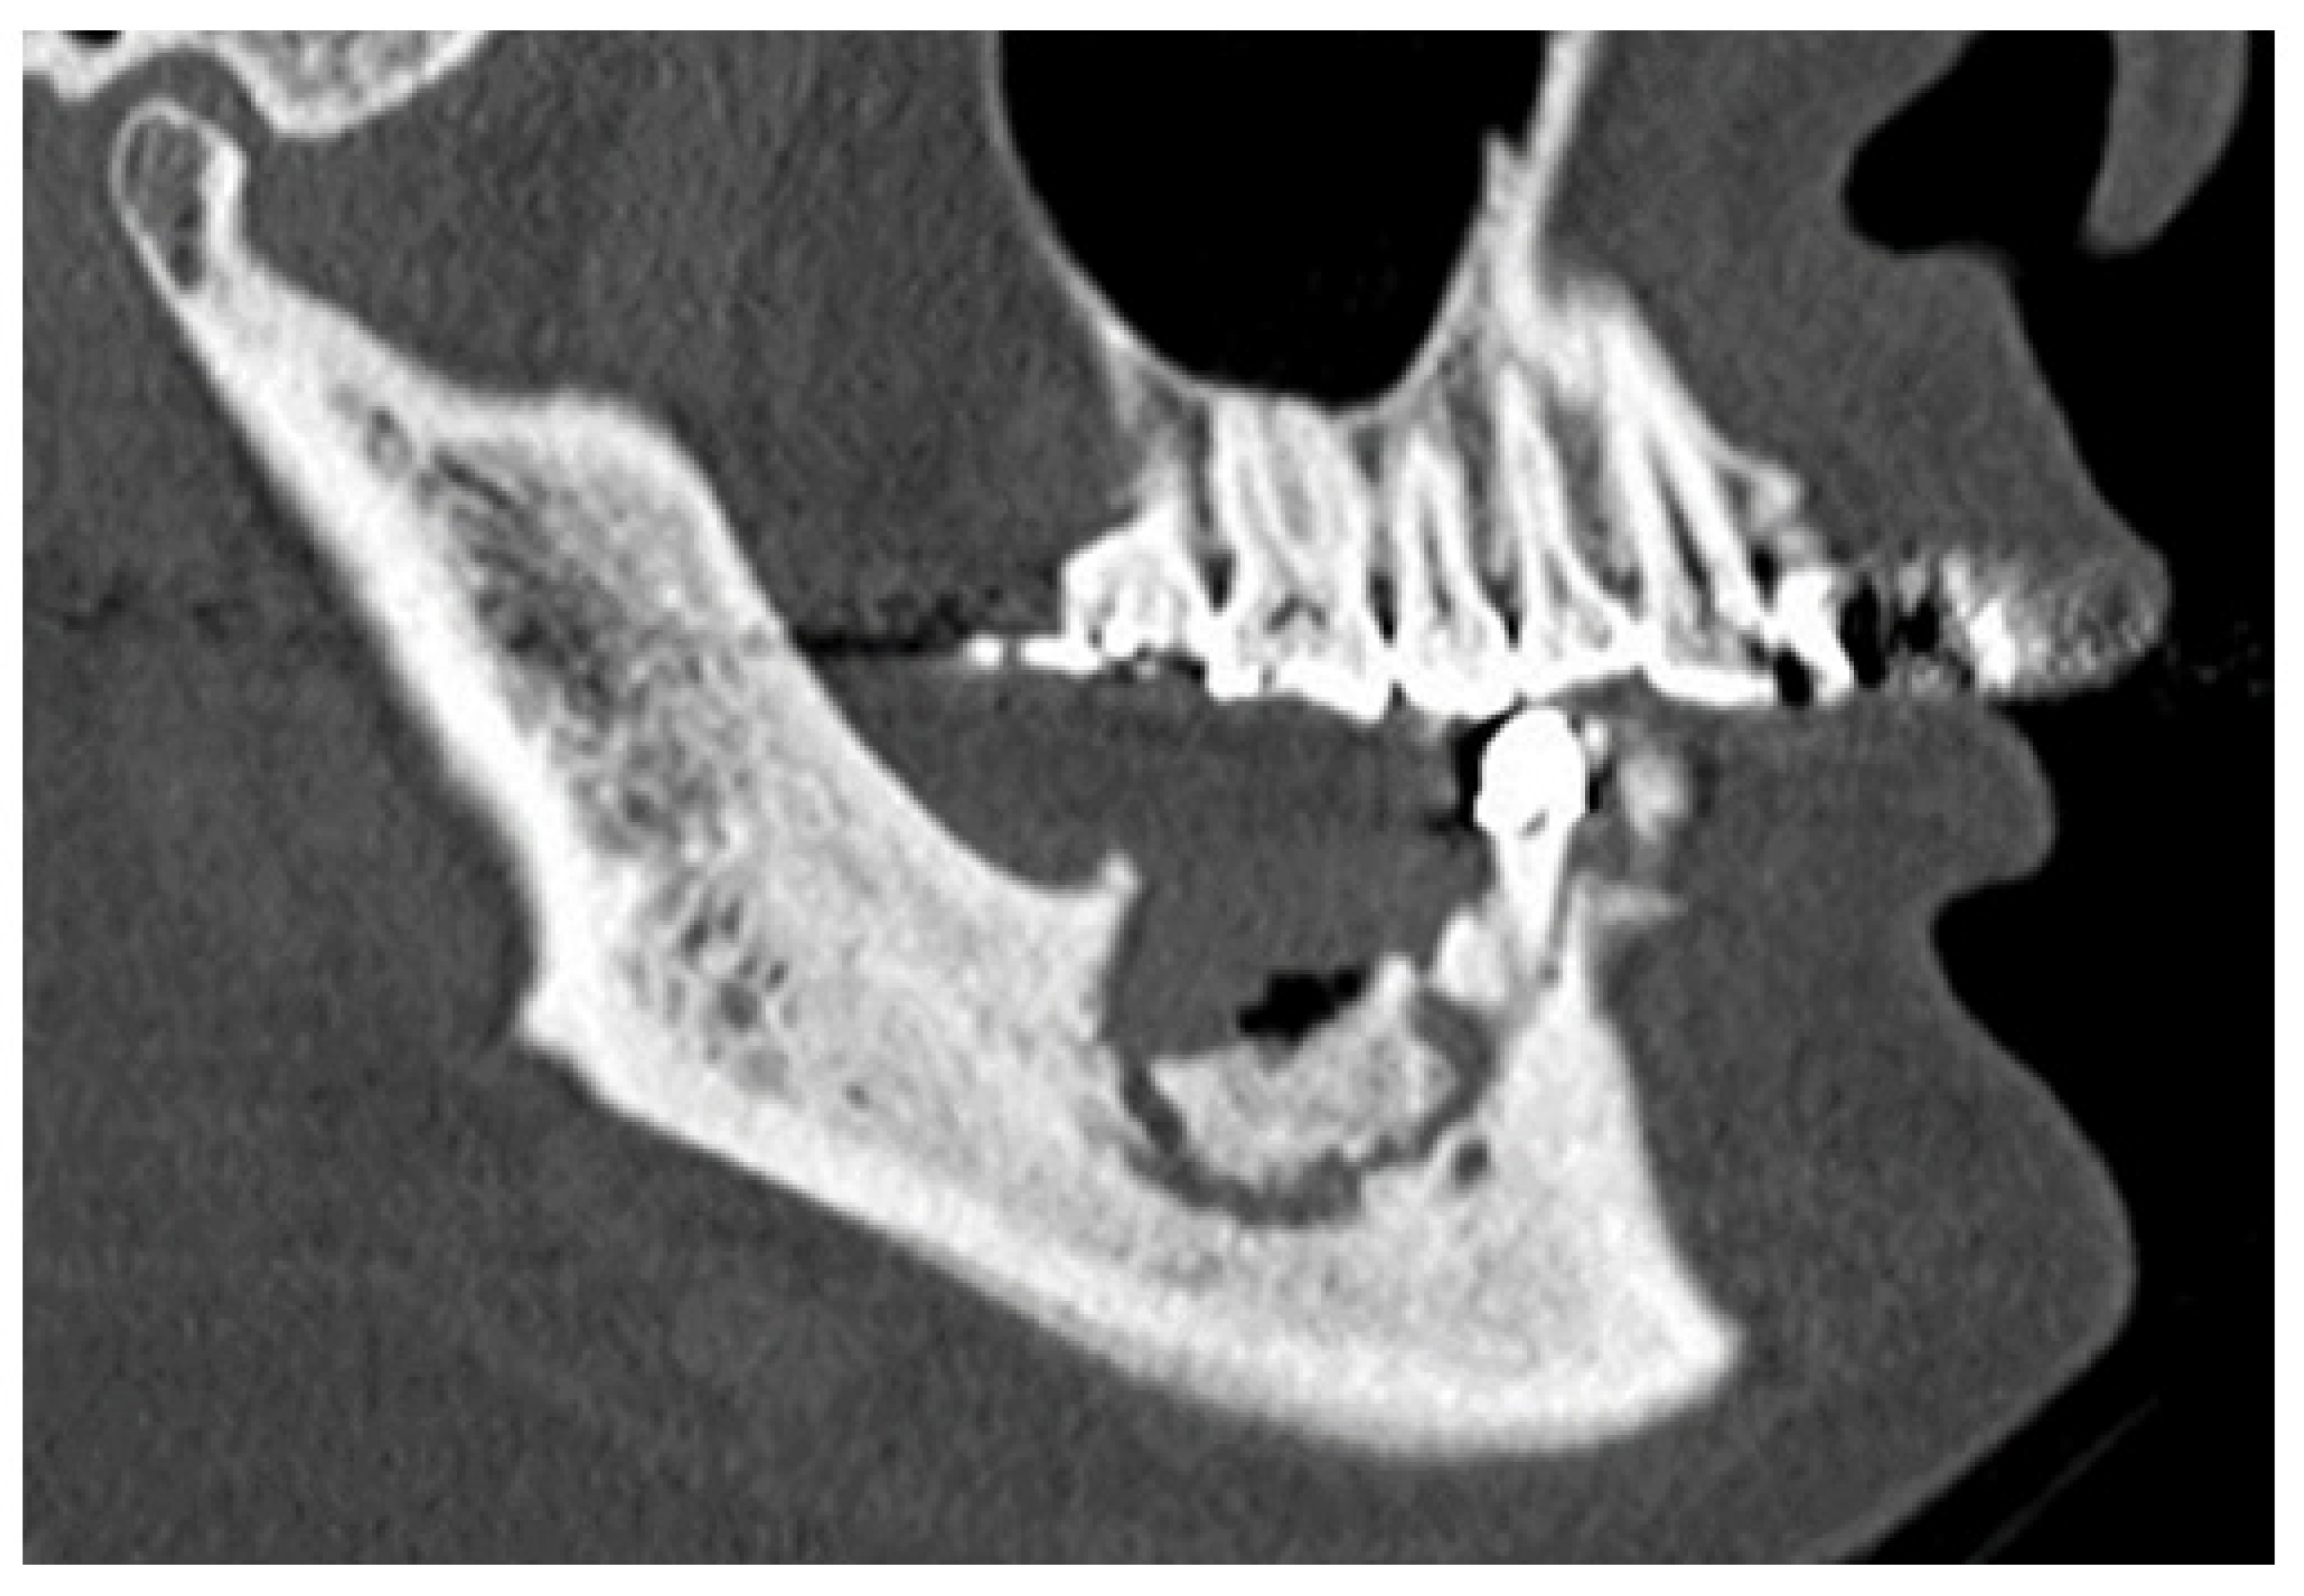

3. Results

3.2. Factors Related to Separation of Sequestrum